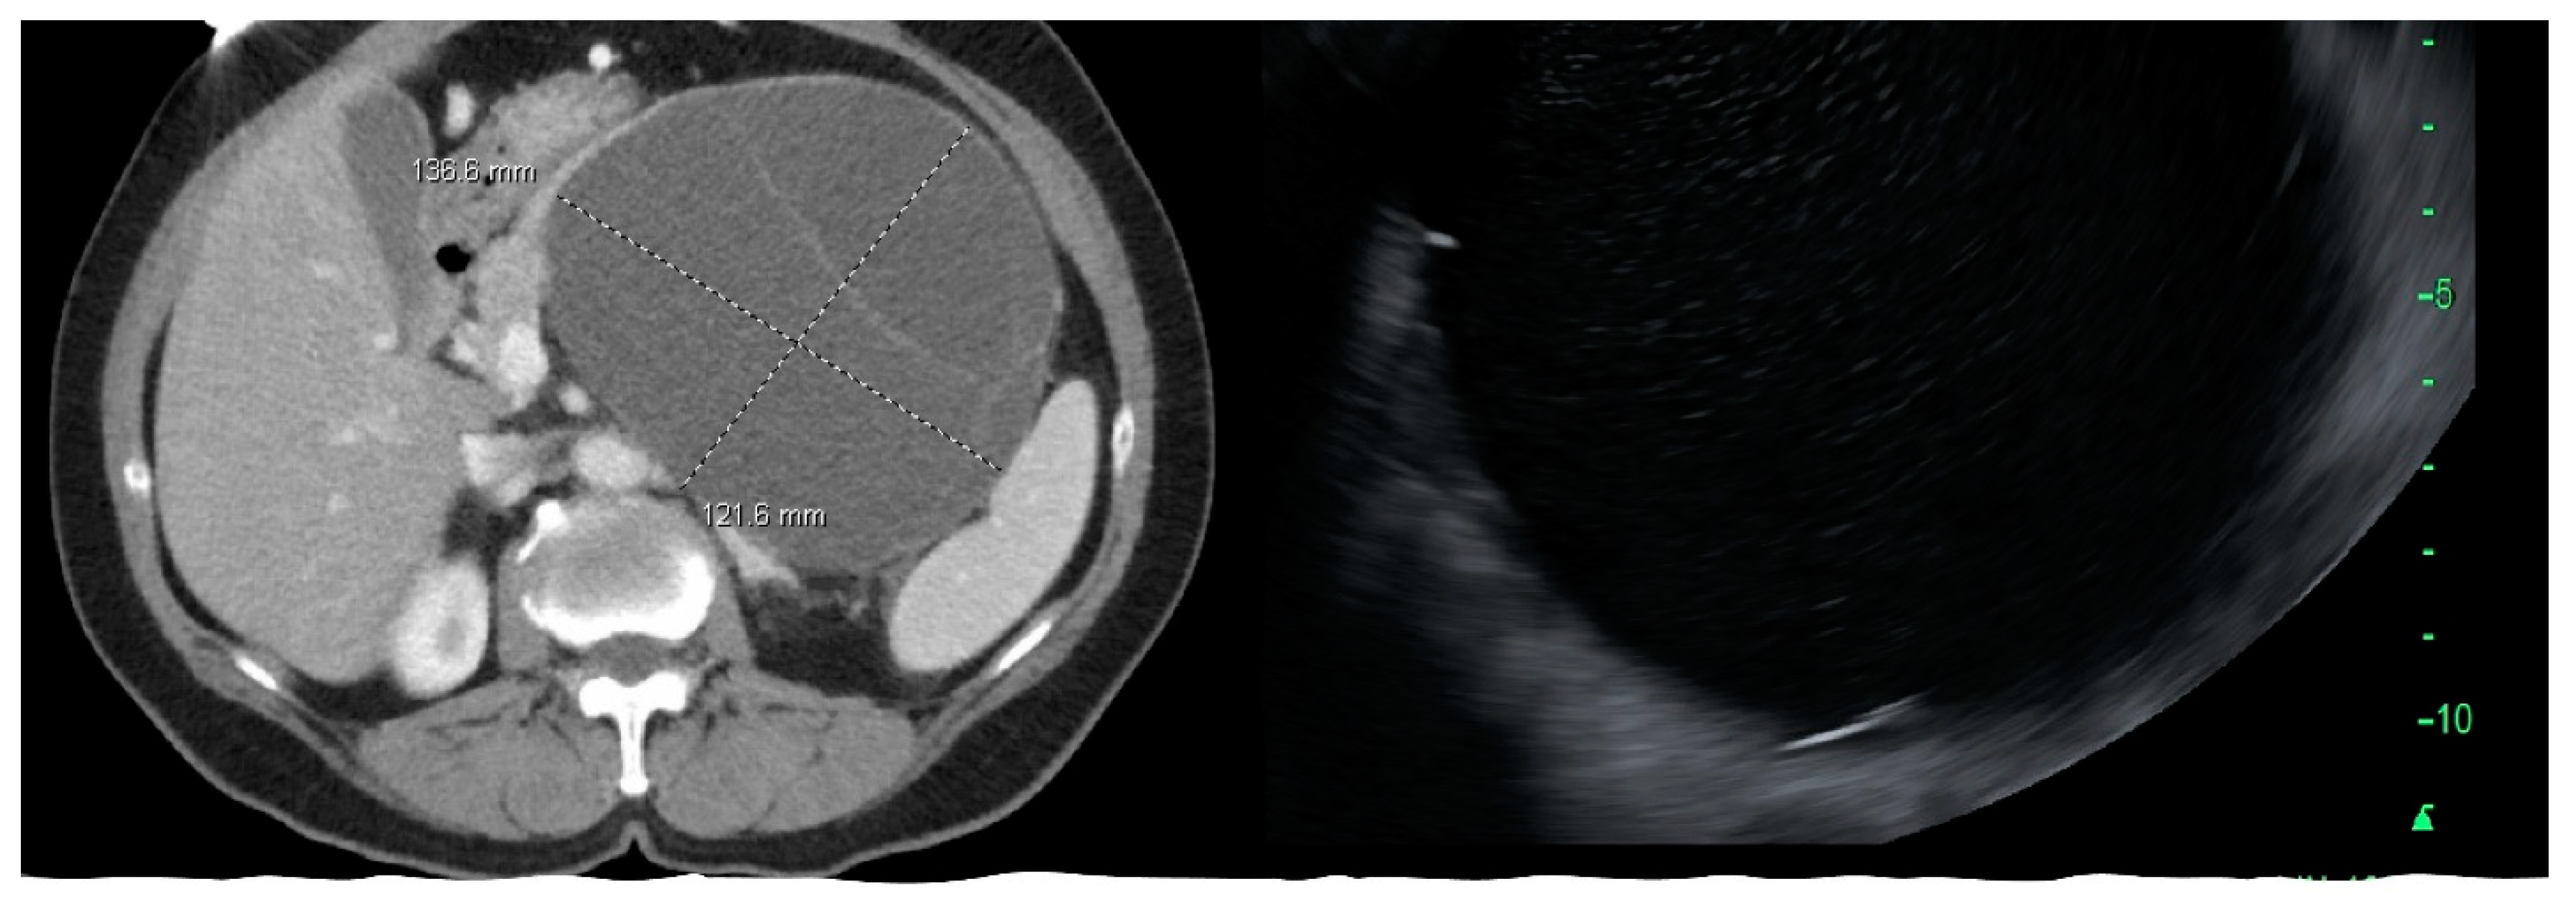

Figure 3.

CT scan and endoscopic ultrasound images of mucinous cystic neoplasm in the body and tail of pancreas.

MCN, SCA, and SPN are solitary cysts. MCN and SCA lack communication with the main pancreatic duct and do not show pancreatic duct dilation on imaging. IPMN, by definition, demonstrate communication with the pancreatic duct, have the dilation of the duct, and are commonly multiple. IPMNs are more common in the head and neck region but can be found in other locations (Figure 2). They can be multifocal and should be considered along with pseudocysts when multiple cysts occur in the pancreas. MCNs are exclusively seen in the body or tail of the pancreas (Figure 3). While SCA can occur in the head, most SCA are located in the body or tail (~70–75%). There is no specific location of SPN (Table 1).

Cyst morphology can provide some insights into the type when characteristic features are present. SPN are characterized by the presence of solid components in the form of a mural nodule. A noticeable feature of SCA, found in about a quarter of cases, is the presence of calcification within the cyst, and this is distinct from the peripheral calcification that can be seen in MCN and SPN (Figure 4). This is sometimes referred to as a “central scar.” Side-branch and mixed-type IPMN are multiloculated and appear as clusters, while main-duct IPMN usually does not demonstrate a prominent cyst but are seen on imaging as a diffuse dilation of the main pancreatic duct.